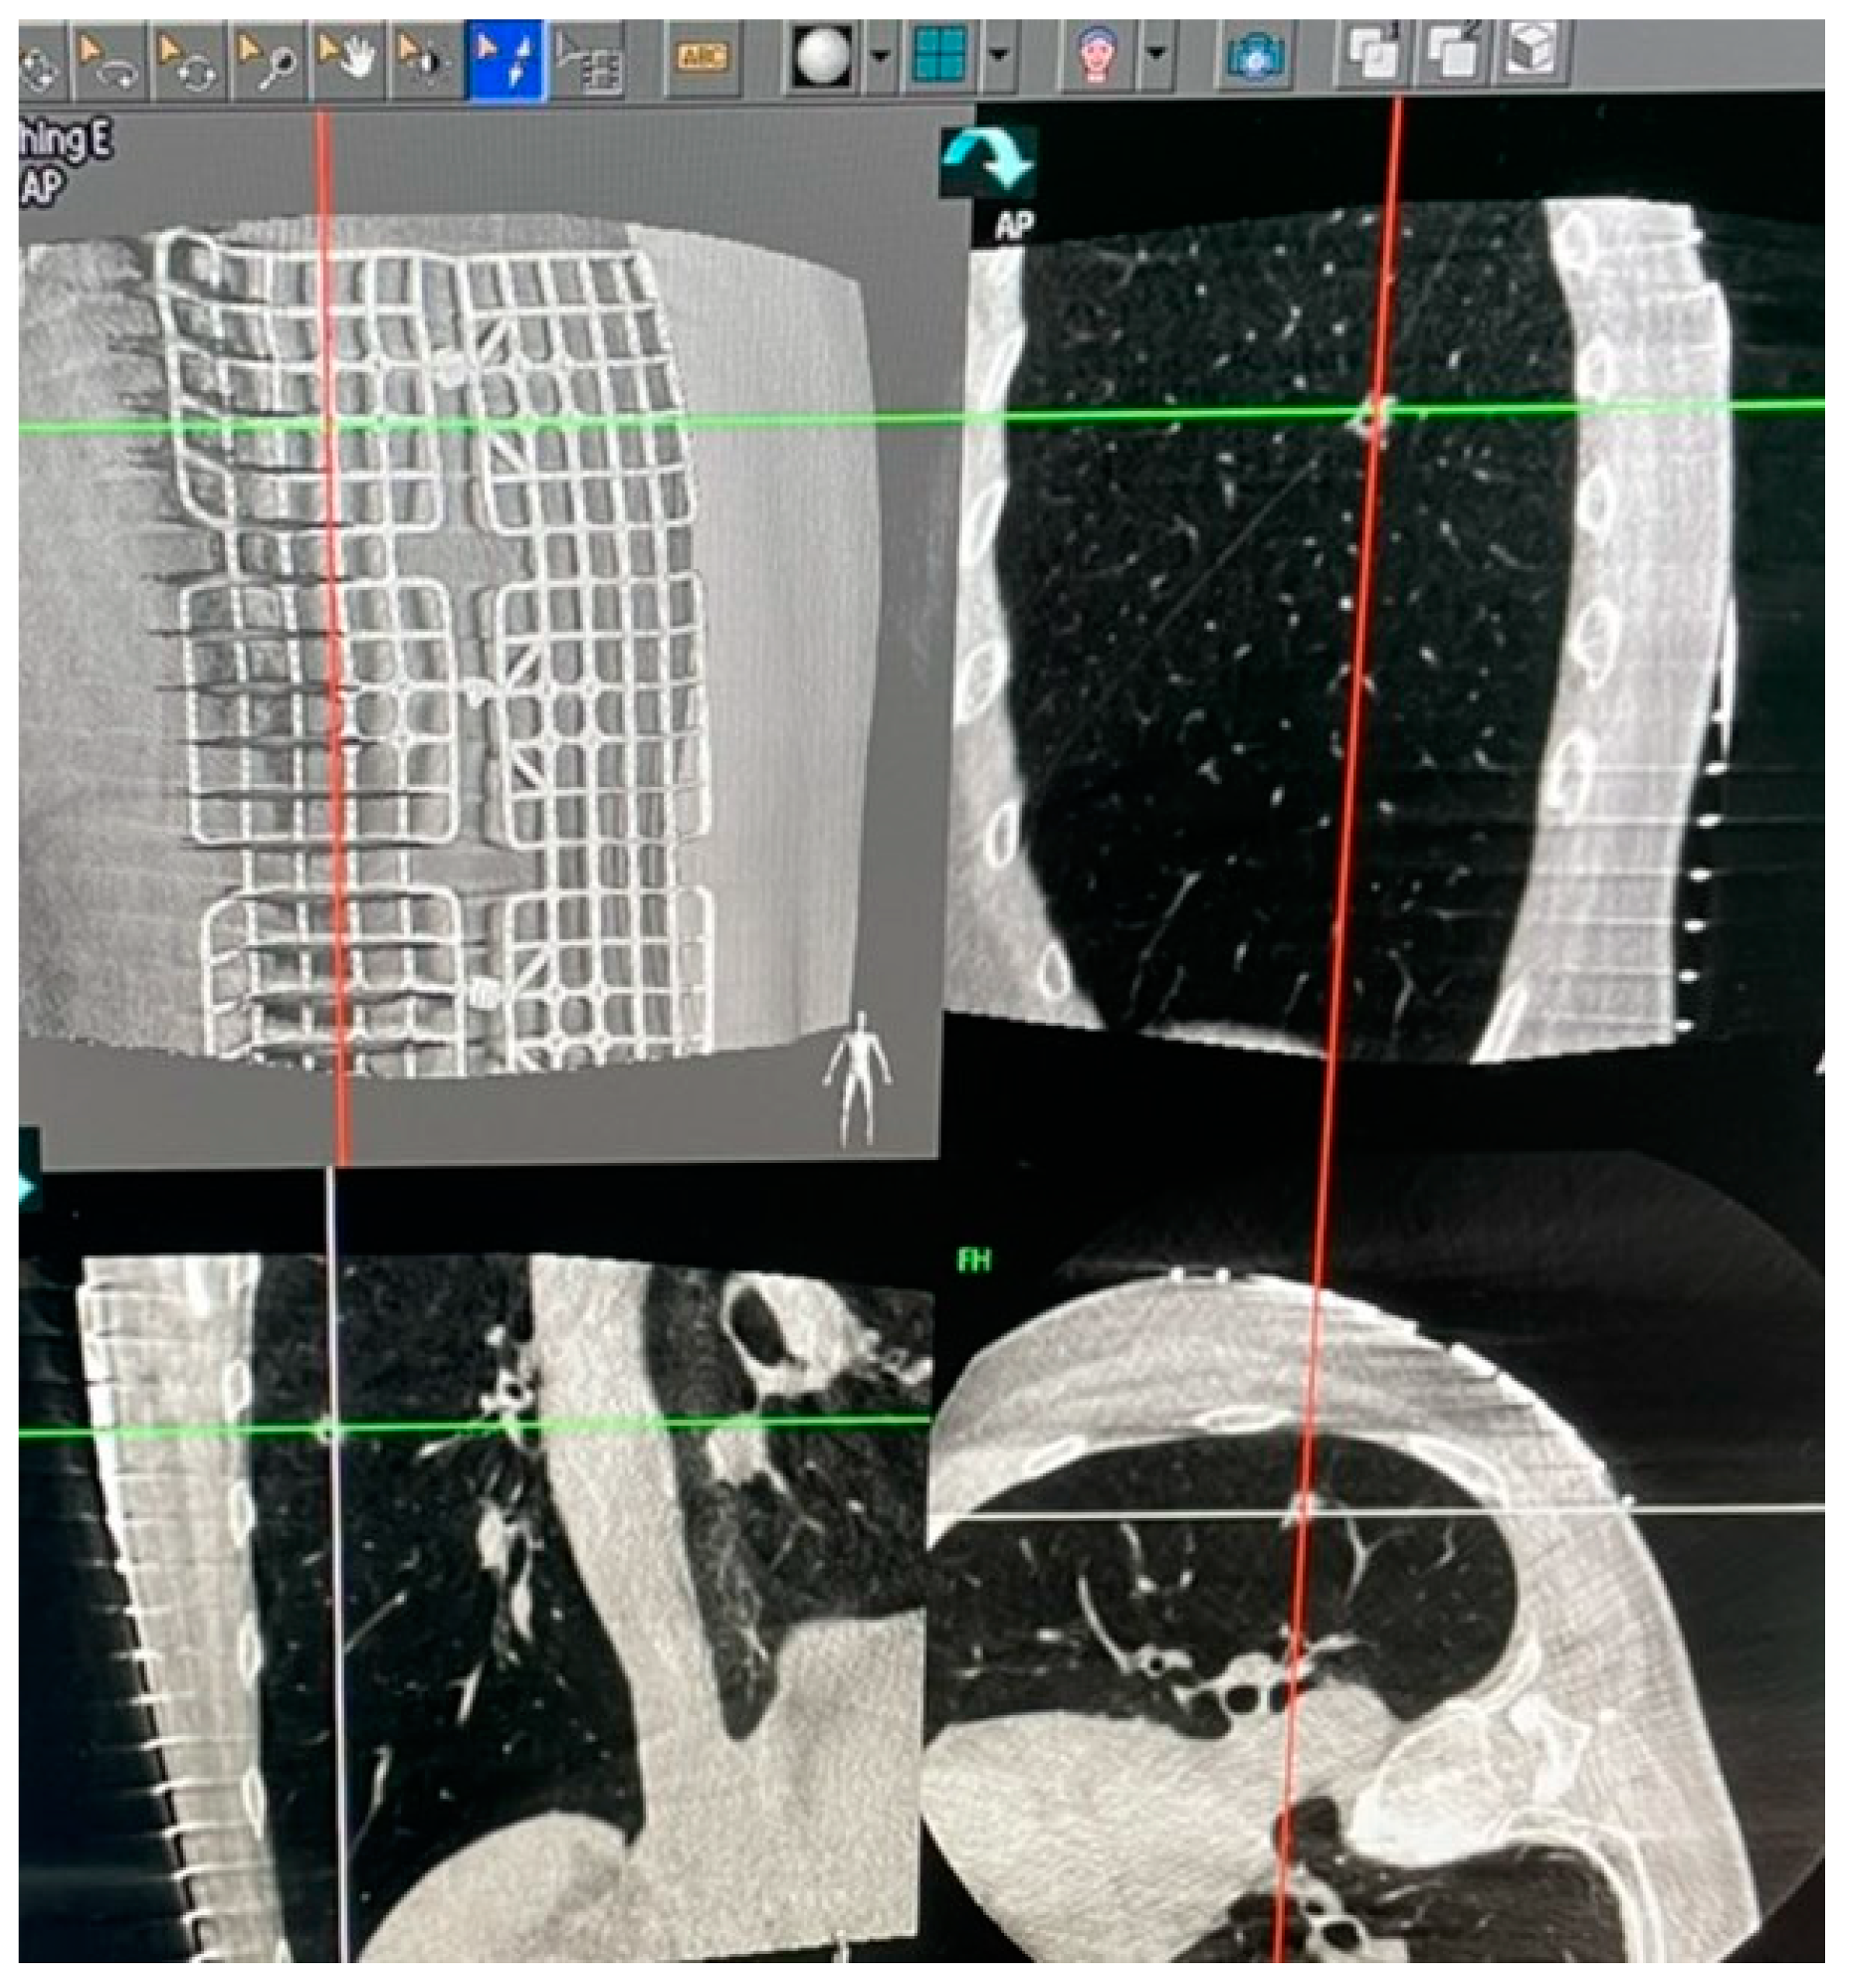

Figure 2. Grid placed on the chest wall for localization.